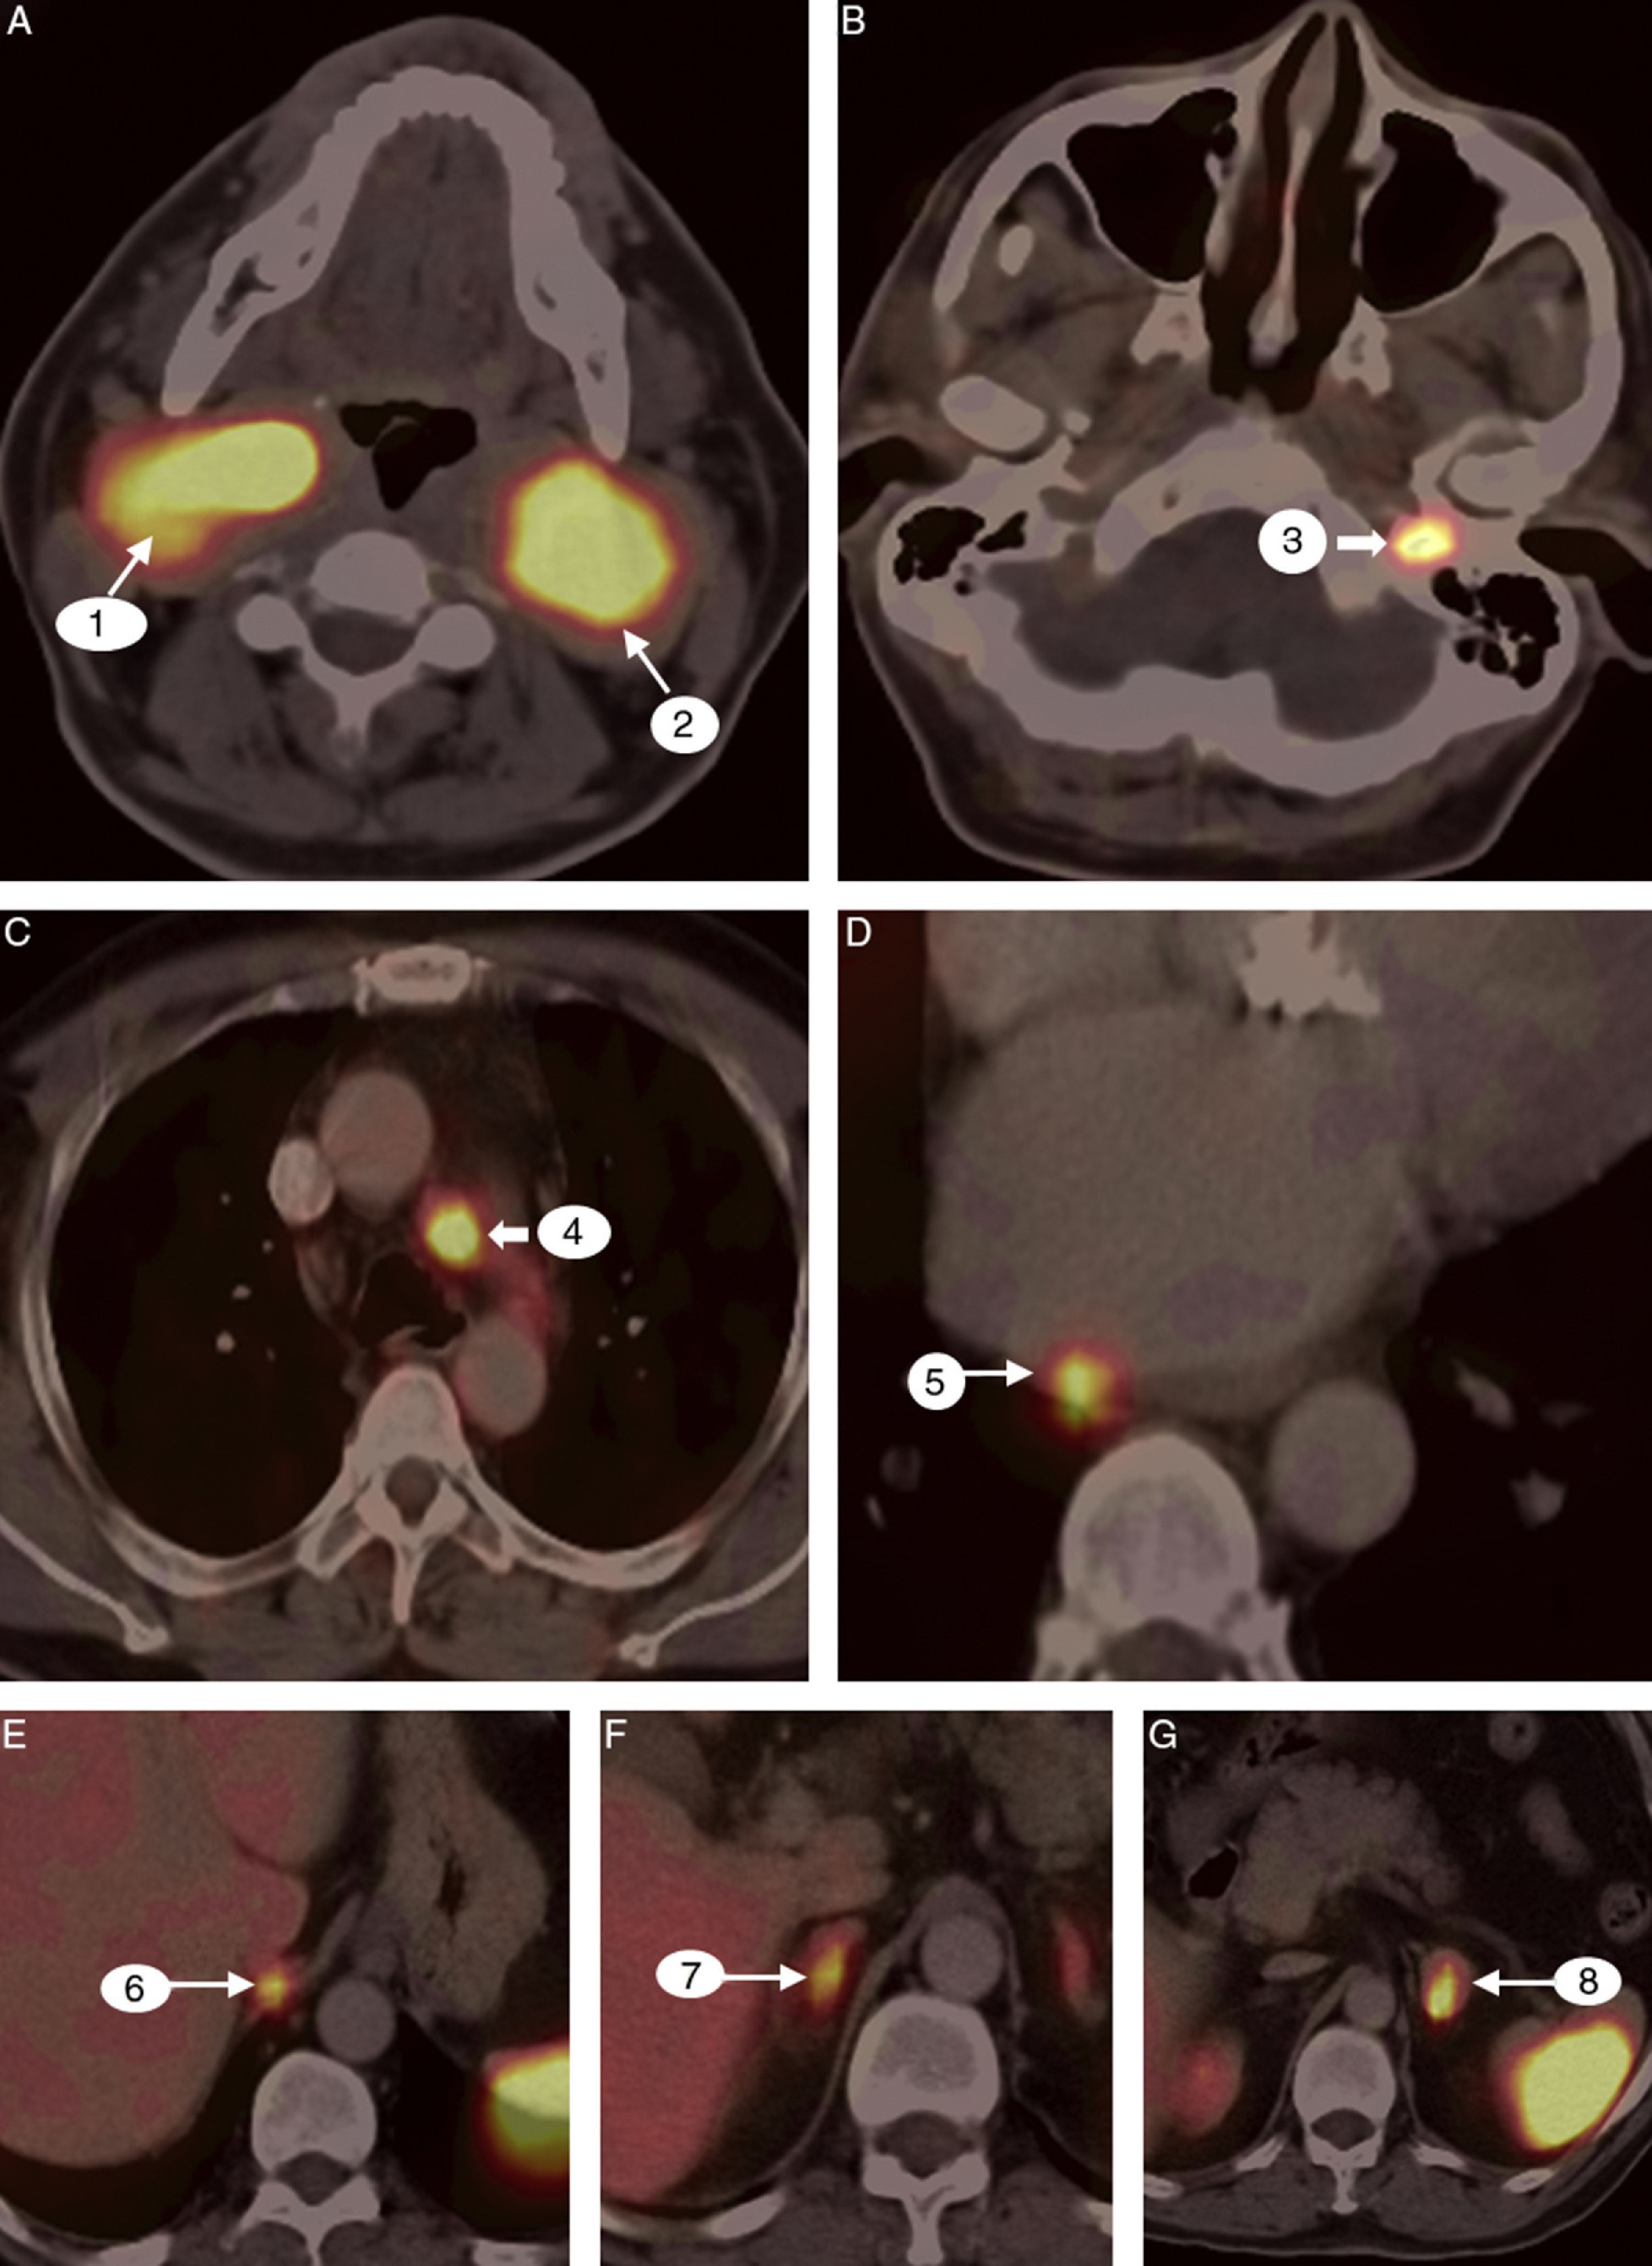

Paragangliomas, or glomus tumors, are neoplasms arising from extra-adrenal chromaffin tissue. They frequently cause symptoms by over-production of catecholamines with known predilection to multicentricity. We describe the case of a patient with bilateral carotid body tumor who underwent a preoperative 68Gallium labeled [1,4,7,10-tetraazacyclododecane-1,4,7,10-tetraacetic acid]-1-NaI3-Octreotide (68Ga-DOTANOC) positron emission tomography/computed tomography (PET/CT) imaging for staging. This is a unique case in which multiple paraganglioma and pheochromocytoma were demonstrated in a single patient using 68Ga-DOTANOC PET/CT.